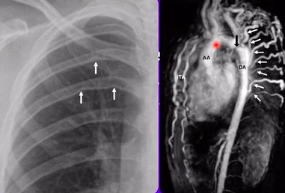

Quando desconfiar de coarctação de aorta como causa de HA secundária?

A

• PA e pulsos reduzidos em MMII (pelo menos 10 mmHg)

• RX tórax: corrosão de costelas (artérias intercostais colaterais para irrigar mmii)

• ECO e/ou angioTC de tórax